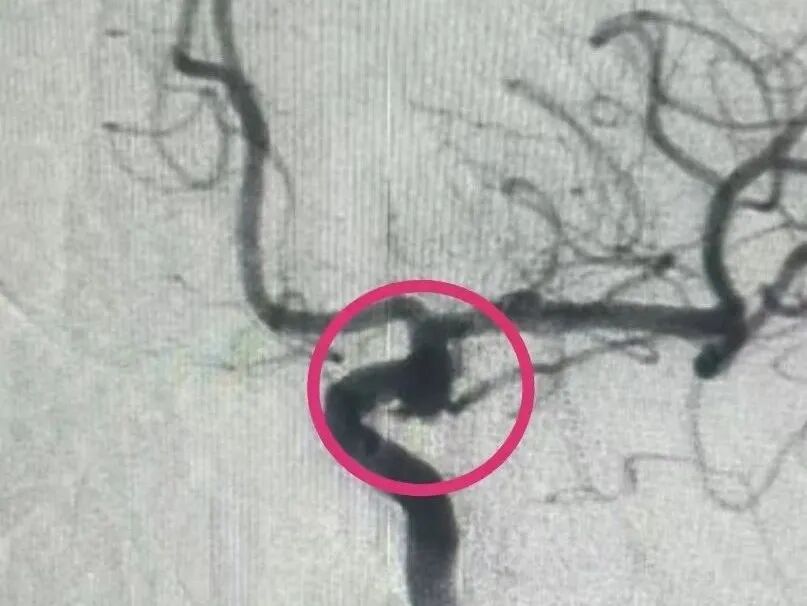

手术在万学录主任的主持下,神经内科三病区王世超医生、神经重症张亚娜医生与郑大一附院杨杰教授密切配合,凭借丰富的经验和精湛的技术,成功地完成了血流导向密网支架植入,治疗过程仅10余分钟!即刻造影便可见瘤内造影剂部分滞留,不久动脉瘤就会完全愈合。术后高阿姨恢复良好,现已康复出院。